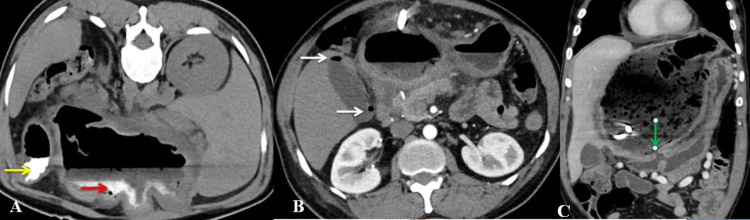

The cyst’s fistulous communication with the duodenum was demonstrated with oral contrast CT scan (Figure 2). The cyst was closely related to the stomach and had displaced the stomach and spleen laterally. The pancreas appeared normal.

Abdominal USG may show anechoic cyst, multiseptate cyst, floating membranes within the cyst, daughter cysts, and calcifications. If the cyst gets secondarily infected, it will lose its characteristic appearance [ref. 2]. Based on the USG appearance, these hydatid cysts have been classified by Gharbi et al. into five categories and WHO Informal Working Group on Echinococcosis (WHO-IWGE) into six categories [ref. 7,ref. 8]. The CT scan of the abdomen shows the location of the cyst, thickness of the wall, presence of daughter cysts, floating membranes, and calcifications if any. Both these imaging techniques usually will not be able to show any CBC if present. The presence of air within the cyst, which both imaging techniques can see, should be highly suggestive of the presence of cystoenteric fistula. In our patient, there was a large hypoechoic cyst with debris and air within it. CT showed debris in the dependent region with an air-fluid level with few membranes in the inferior aspect. The cyst had communication with the duodenum, and there was a presence of air within the gallbladder, with normal CBD without any air. We also hypothesize that the air in the gallbladder was due to duodenal fistulization of the cyst with preexisting CBC. Air must have entered in the biliary radicals and then into the gallbladder through the cystic duct.